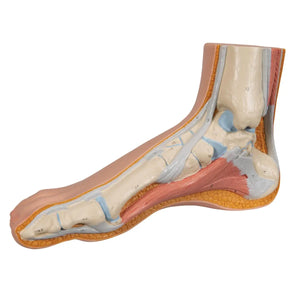

Product information

Skeleton of a normal foot

In addition to the superficial structures, bones, muscles and ligaments are represented and numbered on the internal side.

Skeleton of a normal foot

In addition to the superficial structures, bones, muscles and ligaments are represented and numbered on the internal side.

Skeleton of a normal foot